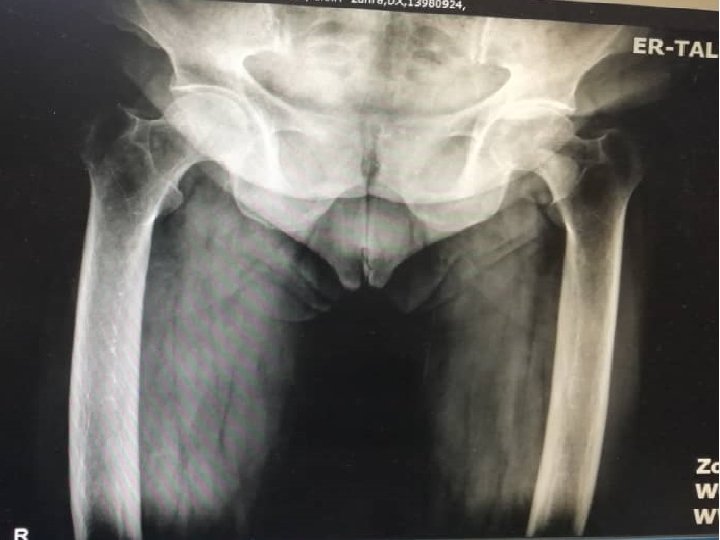

She had intermittent flank pain and hematuria from 2 years ago. She had also epigastric pain from 6 months ago exacerbating with eating and not improved with PPI. She had constipation from many years ago and hadn’t diarrhea, history of fx, weight loss, polyuria and polydipsia Because of right lower thigh pain and her laboratory(ca: 10. 3, p: 2. 9, PTH: 440, 25(OH)Vit. D: 15)wi th primary hyperparathyroidism diagnosis admitted to Taleghani hospital for further workup and treatment.

Imaging report